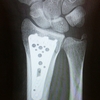

テトラから転落・骨折・経過その2

テトラから転落して25日、骨折の手術してから19日経ちました。釣りのブログのはずが、骨折ブログになっておりますが・・・。生活面はほぼ大丈夫です。釣りもおそらく大丈夫でしょう。でも、もう少し辛抱します。心と体と環境が整うまでと申ししましょうか。